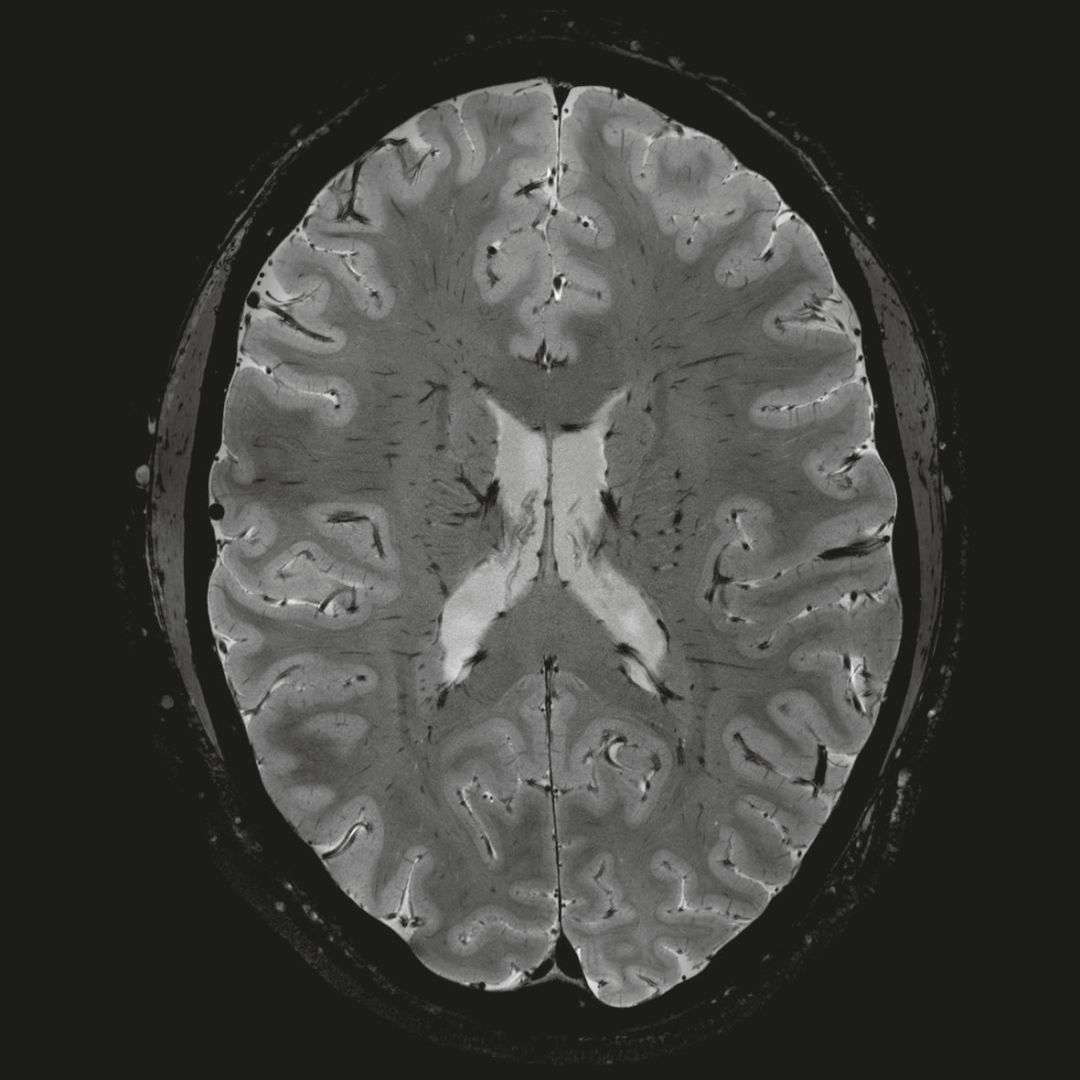

超精細(xì)的解剖細(xì)節(jié):T2對比

0.17 x 0.17 x 0.8毫米分辨率超高。

0.8毫米的各向同性分辨率:精確劃分灰質(zhì)和白質(zhì)

0.8毫米的各向同性分辨率:超精細(xì)的解剖細(xì)節(jié),例:小腦的精細(xì)結(jié)構(gòu)